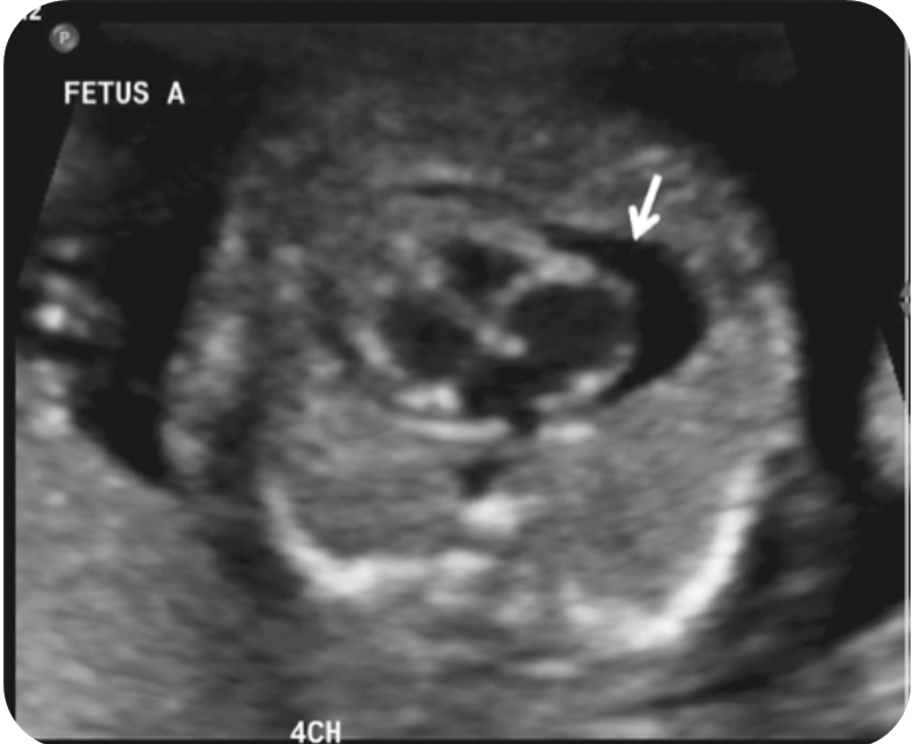

What view is this?

outflow tract

4 chamber view

Normal 4 chamber view